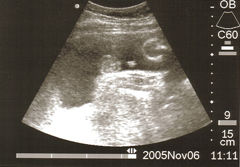

La mujer obesa tiene una predisposición a padecer hipertensión arterial durante el embarazo; además, el exceso de grasa corporal hace mucho más difícil la correcta visualización del feto mediante ultrasonografía, dificulta la amniocentesis diagnóstica, complica la elección de la técnica anestésica, aumenta el riesgo de complicaciones quirúrgicas, multiplica el riego de infecciones por herida y subyuga el tratamiento antibiótico de las infecciones urinarias por vía ascendente.